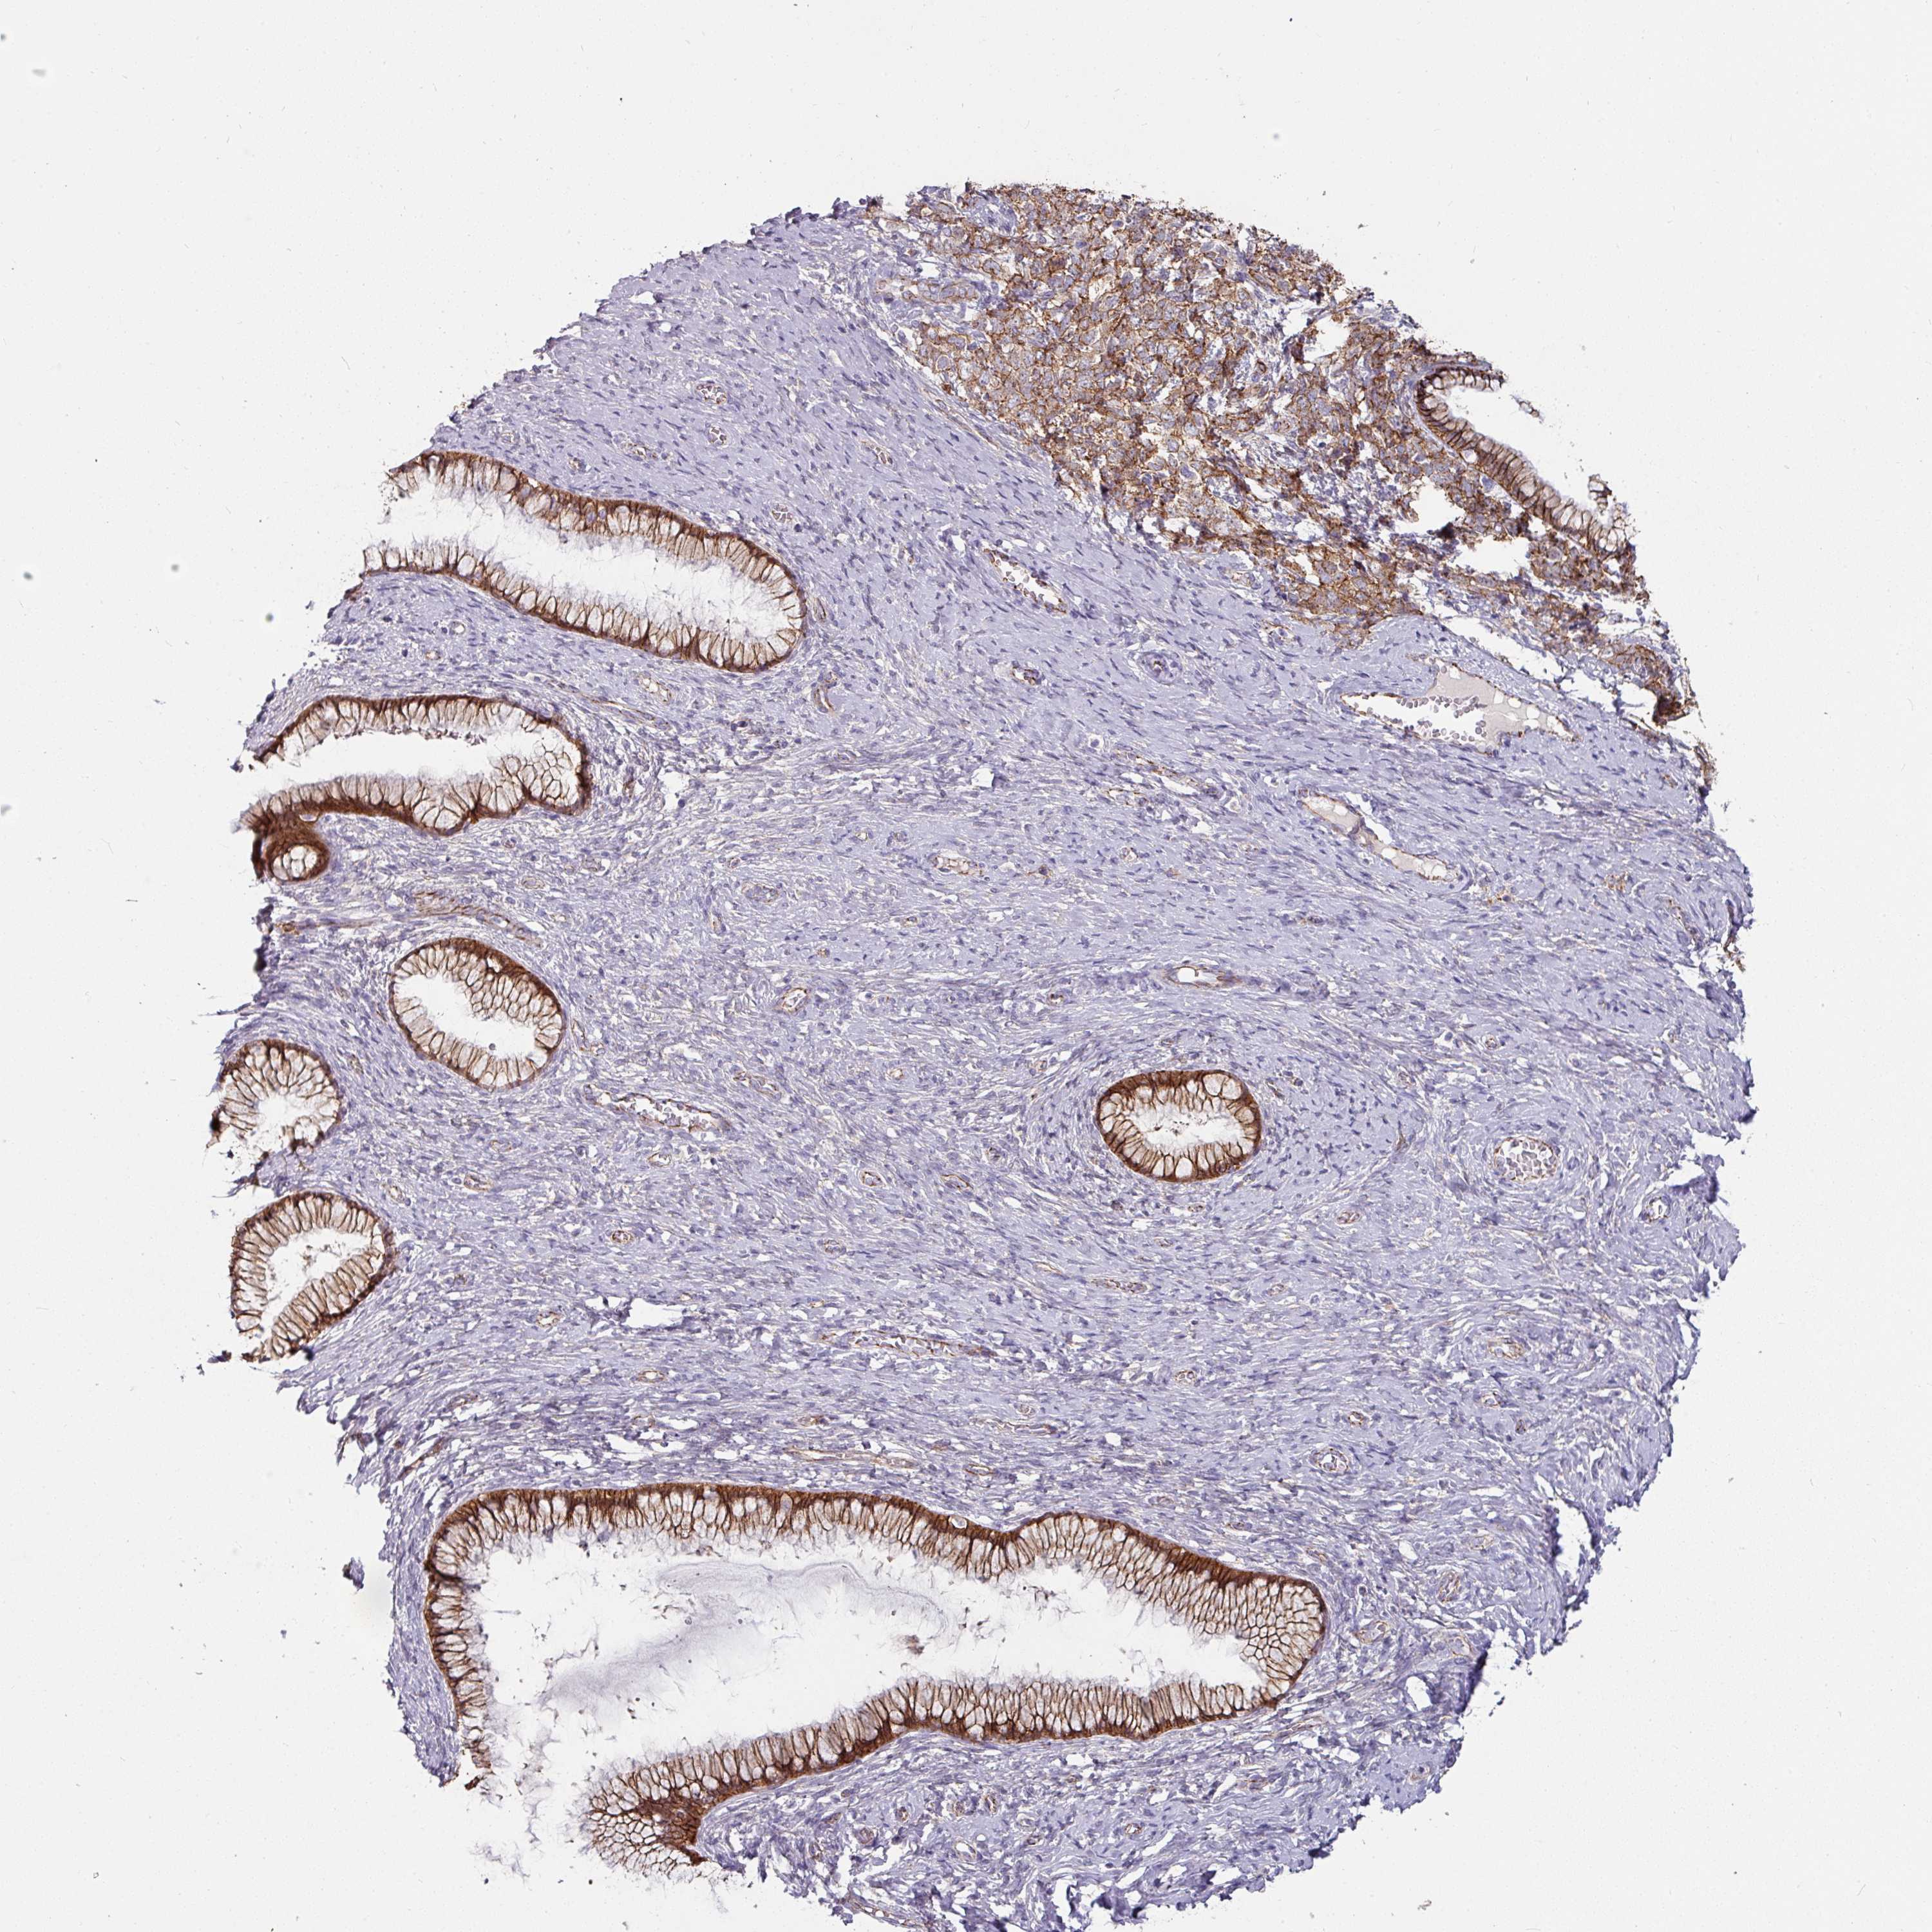

CERVICAL CANCER - Protein expressioni

A mouse-over function shows sample information and annotation data. Click on an image to view it in a full screen mode. Samples can be filtered based on level of antibody staining by selecting one or several of the following categories: high, medium, low and not detected. The assay and annotation is described here.

Note that samples used for immunohistochemistry by the Human Protein Atlas do not correspond to samples in the TCGA dataset.

Antibody stainingi

Antibody staining in the annotated cell types in the current human tissue is reported as not detected, low, medium, or high, based on conventional immunohistochemistry profiling in selected tissues. This score is based on the combination of the staining intensity and fraction of stained cells.

Each image is clickable and will lead to virtual microscopy that enables deeper exploration of all samples and also displays staining intensity scores, fraction scores and subcellular localization as well as patient and tissue information for each sample.

Antibody HPA032047

Antibody CAB002139

Squamous cell carcinoma, NOS